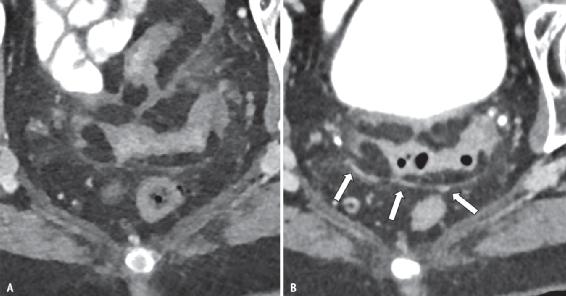

图2 74岁男性,临床诊断为特发性非特异性间质性肺炎,采用临床常规方案在常规EID-CT(A)和PCD-CT(B)上进行扫描。

A、B 与常规CT相比,PCD-CT显示右胸膜下右下叶的精细网状结构(箭头,B),常规CT显示该区域的毛玻璃样阴影(箭头,A)。光子计数探测器比常规CT更清晰地显示牵引性支气管扩张(箭)。

图3 56岁男性,患有多发性骨髓瘤。

A、B 通过胸椎的轴位能量积分探测器CT(A)和PCD-CT(B)切片。在PCD-CT图像上可以更清楚地看到胸椎溶解性病变。椎体后部的溶解性病变(后皮质破裂)更清晰(虚线箭头)。在PCD-CT图像上,椎体中较小的溶解性病变(箭头)更为明显。